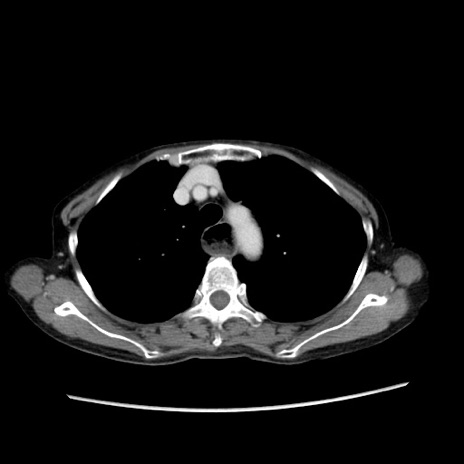

症例25(横断像)

【症例】80歳代女性

【主訴】胸のつかえ感

【現病歴】約9時間前に食後から胸のつかえた感じあり、嘔吐あり、来院。

【既往歴】胃癌(全摘)、胆摘、虫垂炎

【身体所見】心窩部に圧痛あり、反跳痛なし。

【データ】WBC 5700、CRP 0.05